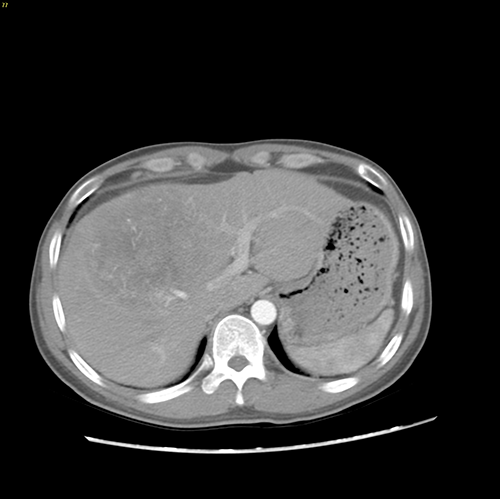

右肝癌---右三肝切除